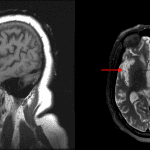

- Marked age-advanced frontal and temporal lobe volume loss with ex vacuo enlargement of the lateral ventricles

- The degree of atrophy is more pronounced in the right hemisphere relative to the left

- Mild patchy periventricular T2/FLAIR signal hyperintensity

Frontotemporal lobar degeneration (FTLD)

Marked age-advanced frontal and temporal lobe volume loss with ex vacuo enlargement of the lateral ventricles. The degree of atrophy is more pronounced in the right hemisphere relative to the left. These findings raise concern for frontotemporal lobar degeneration (FTLD) with the right-sided predominance most typical for the behavioral variant of frontotemporal dementia.